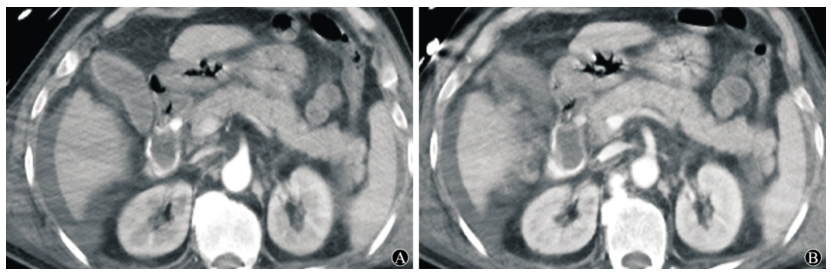

图:胆囊结石、胆总管结石术后 1 个月呕血及黑便;血管造影肝右动脉假性动脉瘤

图:肝门胆管癌PTCD 、胆道支架术后 3 天,引流管反复引出血性胆汁;肝动脉造影未见异常,导丝交换撤出引流管后再次行肝动脉造影,对比剂经引流道外溢至腹腔。

图:造影见胃十二指肠动脉近段动脉瘤,并可见造影剂溢出;弹簧圈栓塞后动脉瘤闭塞。

图:胰十二指肠切除术后11天出现便血和黑便;肠系膜上动脉造影见分支动脉假性动脉瘤。